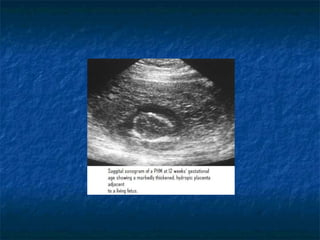

Transverse transpelvic sonogram of a partial hydatidiform mole (PHM) at 16 weeks.

The major imaging feature is the presence of fetal tissue on the left side of the image

and the many small cysts that replace the placental tissue on the right side. This

finding has a distribution more focal than that typically found in CHM.

Partial Hydatidiform mole:PartialHydatidiform mole: Fetal tissue is often present in PHMs, but the fetus is nonviable, it is severelyFetal tissue is often present in PHMs, but the fetus is nonviable, it is severely growth restricted, or it has multiple anomalies. On pathologic analysis, PHMsgrowth restricted, or it has multiple anomalies. On pathologic analysis, PHMs show unpronounced swelling of chorionic villi and unpronounced trophoblasticshow unpronounced swelling of chorionic villi and unpronounced trophoblastic hyperplasia.hyperplasia. Transverse transpelvic sonogram of a partial hydatidiform mole (PHM) at 16 weeks. The major imaging feature is the presence of fetal tissue on the left side of the image and the many small cysts that replace the placental tissue on the right side. This finding has a distribution more focal than that typically found in CHM.